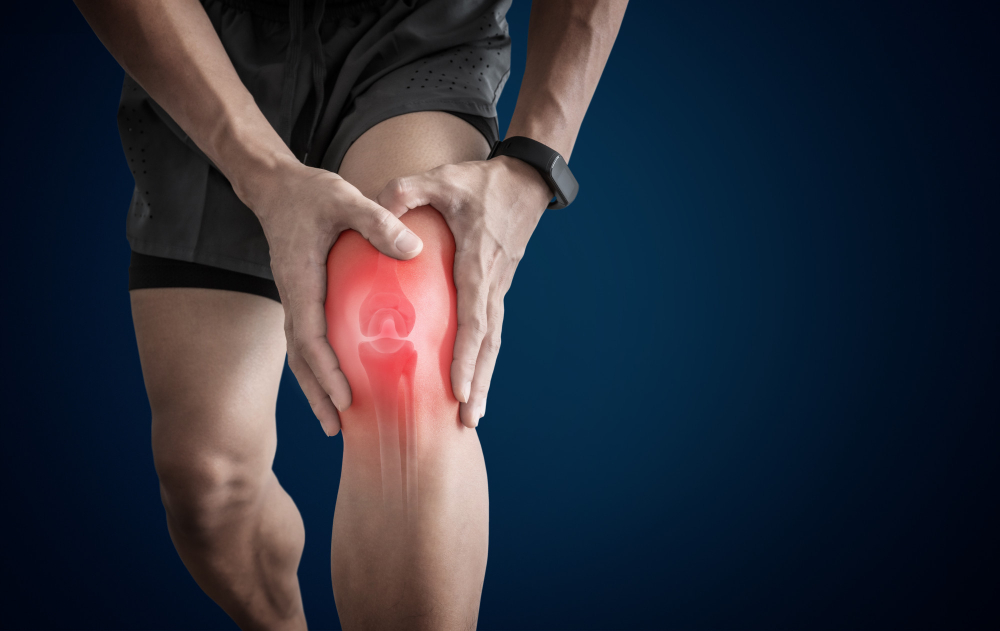

Knee Pain

Knee pain is increasingly becoming a more common problem in society. It is a complaint we see frequently. The most common complaint associated with knee pain is considered the normal “wear and tear.” Another ailment that affects the knee is osteoarthritis. The symptoms and progression of osteoarthritis and knee pain can be reduced through our individualized approach to chiropractic care.